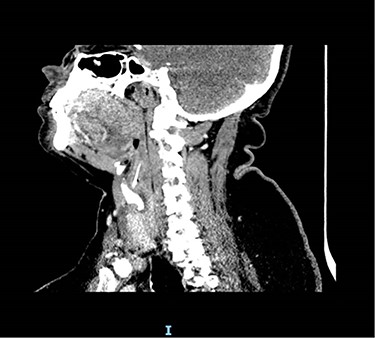

Due to the suspicion of trauma from fishbone ingestion leading to localized swelling and inflammation, a non-contrast computed tomography (CT) scan of the neck was arranged. This revealed a 2.7 cm curvilinear calcific density in the right supraglottic larynx, extending cranially from the anterior wall of the right pyriform fossa, involving the paraglottic fat caudally to the level of the superior aspect of the right vocal cord, 1–2 mm deep to the thyroid lamina and 4–5 mm lateral to the superior surface of the vocal process of the right arytenoid (Figs 1 and 2). The patient was listed for panendoscopy and removal of foreign body.